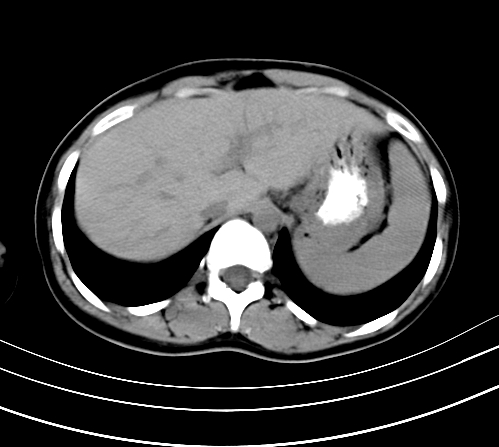

腹部平扫

动脉期